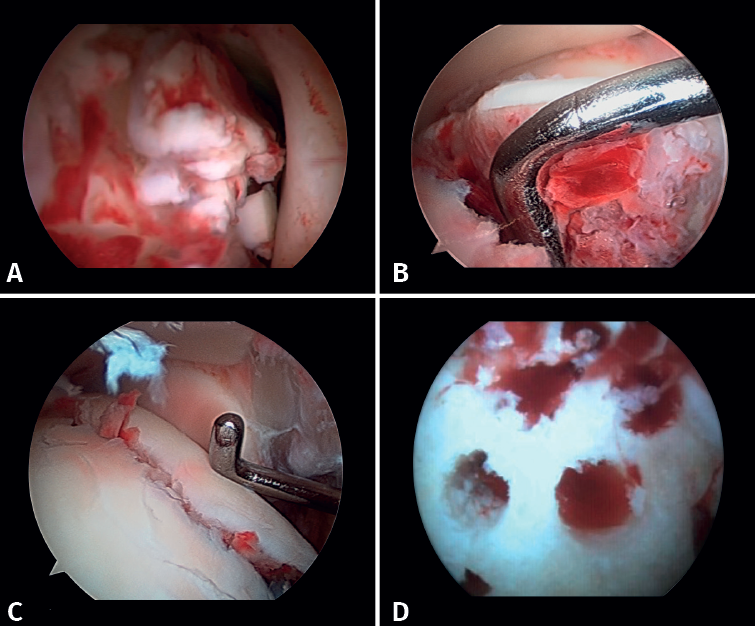

Figura 3. A: cuerpos libres; B: lesión osteocondral; C: reducción de la lesión osteocondral; D: estimulación medular.

Si es posible, realizaremos la reinserción de fragmentos osteocondrales inestables (Figura 3). En las lesiones condrales donde no es posible reinsertar el fragmento, pueden emplearse técnicas de estimulación de reparación del cartílago(5,13).

Lee describe una técnica novedosa que utiliza una guía de broca con la artroscopia de tobillo para la reducción de fragmentos articulares en fracturas del maléolo posterior. En particular, esta técnica es beneficiosa para pacientes con fracturas trimaleolares que presentan un fragmento articular deprimido, ya que permite una reducción anatómica y minimiza la necesidad de incisiones extensas(11). - Extracción de cuerpos libres. La presencia de cuerpos libres dentro de la articulación es un hallazgo común en las fracturas de tobillo. El 33% de los pacientes con artroscopia presentaron cuerpos sueltos intraarticulares retirados durante la intervención (24 de 71 casos)(12). La artroscopia permite la eliminación precisa de los cuerpos libres intraarticulares, los cuales pueden producir dolor, bloqueo o limitación de la movilidad y daño del cartílago articular(13).

- Manejo de las lesiones condrales: la bibliografía reporta tasas entre el 34 y el 91% de estas lesiones en las fracturas de tobillo. Estas lesiones se localizan frecuentemente en el astrágalo y son más comunes en fracturas graves, como las fracturas Weber C y PER. Los pacientes con lesiones del cartílago tuvieron una probabilidad 3,5 veces mayor de desarrollar osteoartritis radiográfica (puntuación de artritis de Kannus < 90) y un riesgo 5 veces mayor de presentar un pronóstico clínico a largo plazo desfavorable (puntuación de la American Orthopaedic Foot and Ankle Society –AOFAS– < 90)(14).